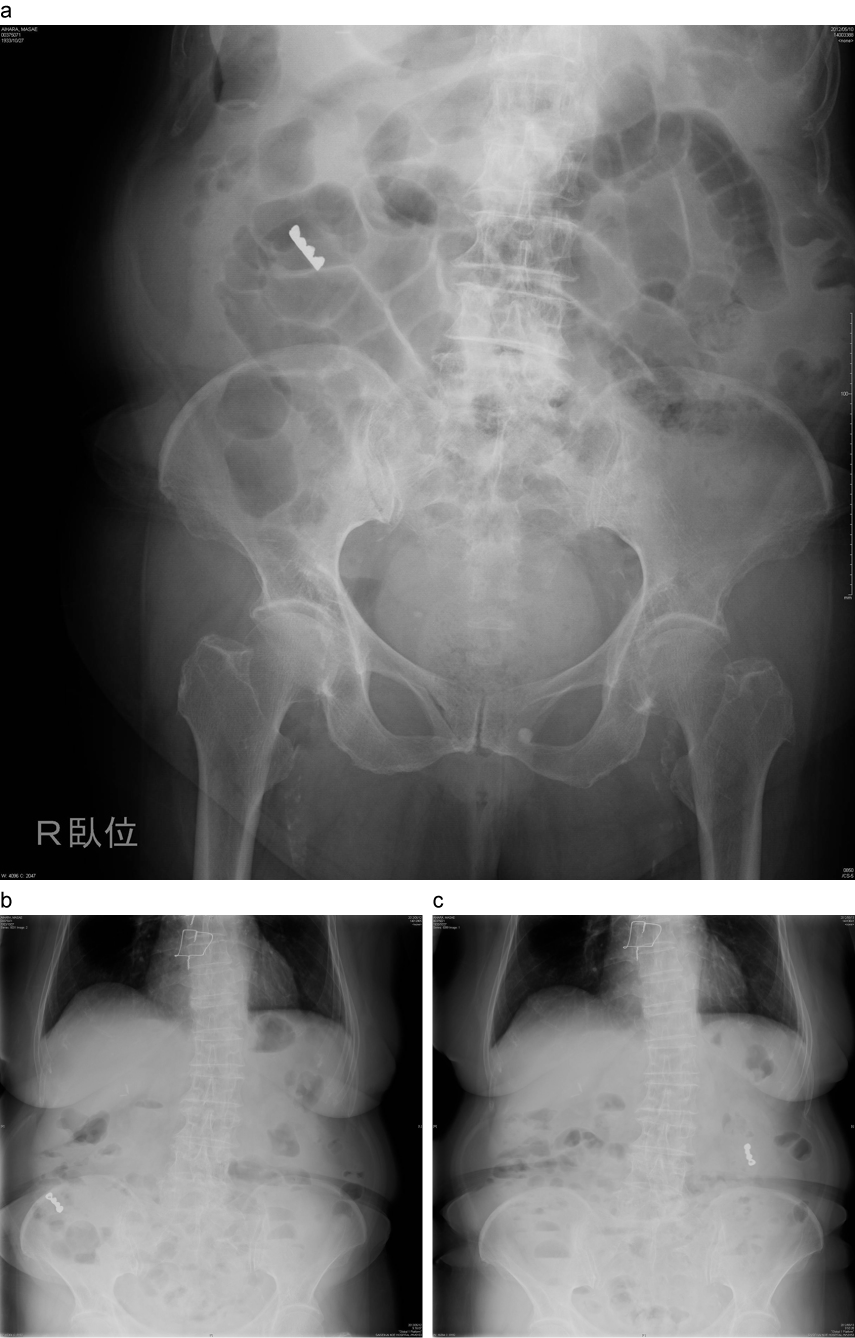

小腸異物(義歯)例

a:上腹部に異物(義歯)を認める。

b:異物によるアーチファクトも強く、十二指腸内か空腸に移行しているか判断が困難であった。

c:同上

異物は空腸へ移動していることが示唆された。

a:経過観察(2日目):異物は肛門側へ進んでいることが示唆される。

b:経過観察(3日目):同上

c:経過観察(4日目):同上 この後、便中に異物(義歯)の排出を確認した。